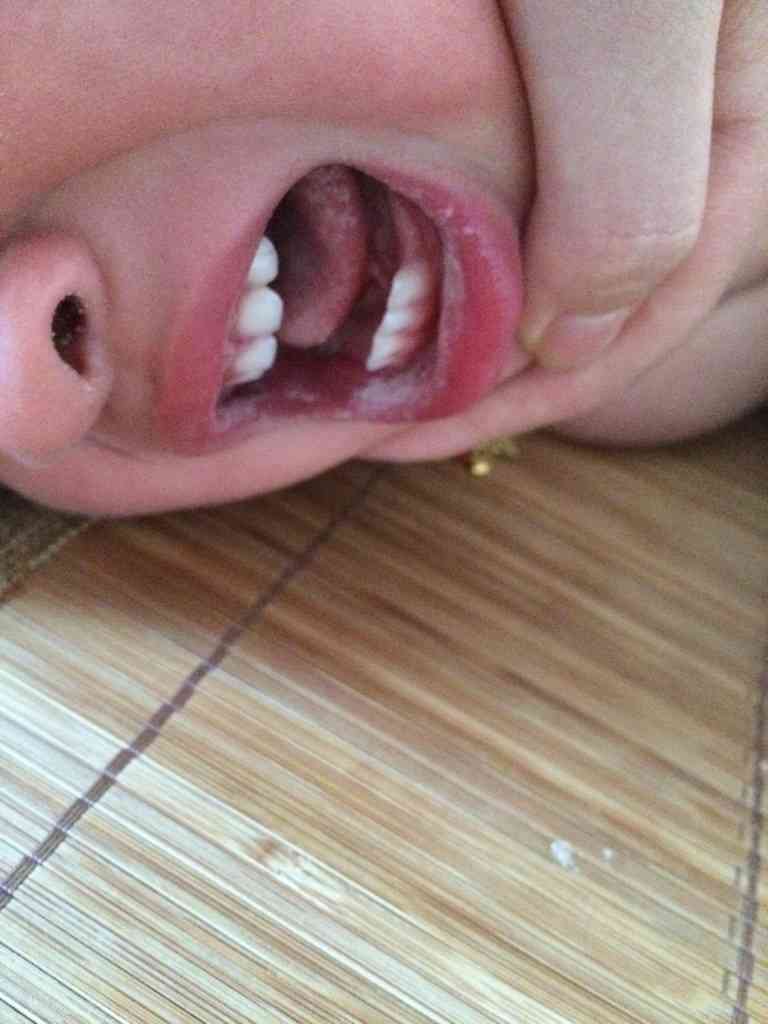

宝宝长的这个是鹅口疮吗.

图片尺寸1920x1440

这是鹅口疮吗?这几天口水流的,一看原来是嘴里长了片白疮

图片尺寸576x1024